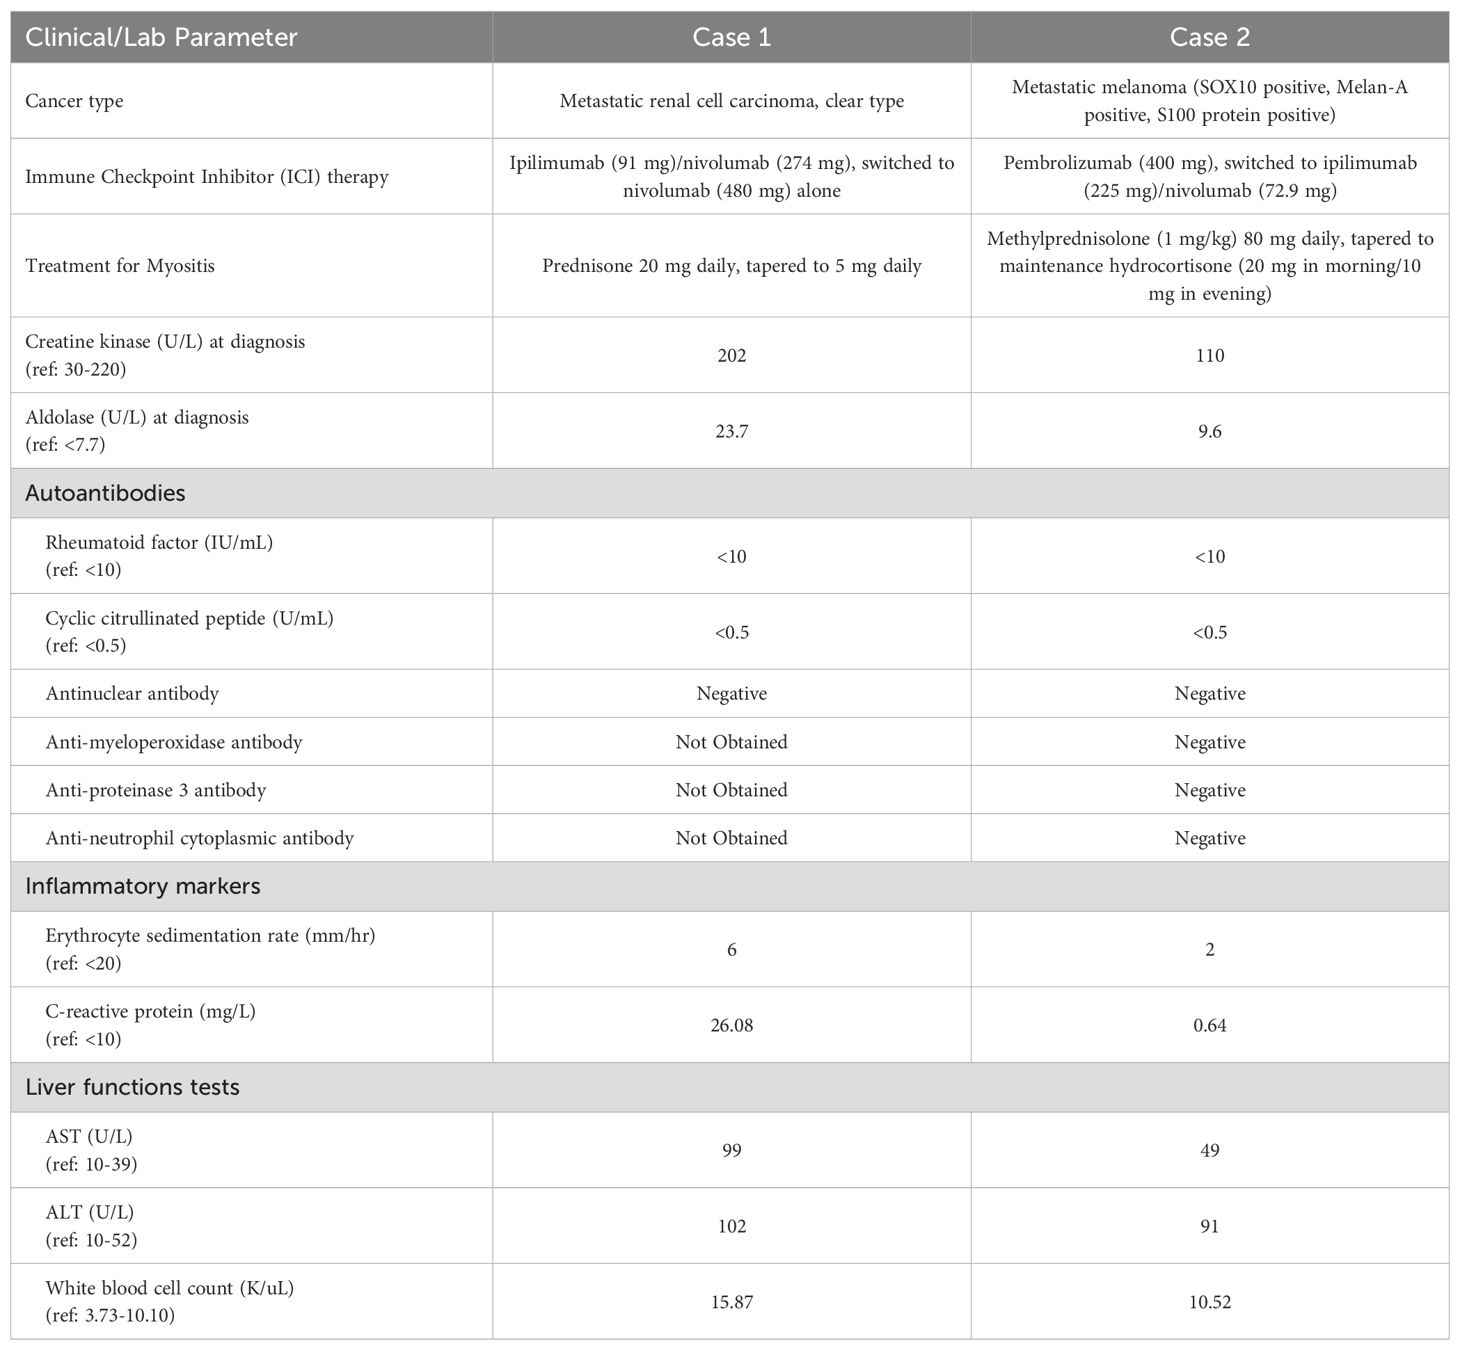

He was started on ipilimumab (91mg)/nivolumab (274mg). He completed 4 cycles (9 weeks) with partial response. He developed grade 2 colitis (per Common Terminology Criteria for Adverse Events [CTCAE], version 5) (3) after the 4 treatment cycles and was switched to nivolumab alone (480 mg). He was treated with a prolonged budesonide taper (entailing 9 mg daily for 2 weeks, then 6 mg daily for 2 weeks, then alternation between 6 mg and 3 mg daily for 2 weeks, then 3 mg daily for 2 weeks, then alternation between 3 mg and 0 mg daily for 2 weeks). This was followed by a prednisone taper (entailing 5 mg daily for 2 weeks, then 2.5 mg daily for 2 weeks). He continued immunotherapy until cycle 7 (33 weeks) after which he developed symptoms of diffuse myalgias, joint stiffness, and fatigue. The CK level obtained at that time was normal (161 U/L). He became unable to perform his activities of daily living requiring hospital admission within that month. This was approximately 5 days after completing the prednisone taper and 8 months after starting nivolumab alone. His labs were notable for white blood cell count (WBC) (15.9 K/uL), C-reactive protein (26 mg/L), elevated transaminases (aspartate aminotransferase [AST], 99 U/L and alanine aminotransferase [ALT], 102 U/L), and normal CK (202 U/L), all of which were collected around 101 days from when budesonide was started. The autoimmune workup including rheumatoid arthritis (RA), and systemic lupus erythematosus (SLE) was negative (Table 1). Viral causes tested included hepatitis C which was negative. A right wrist x-ray was obtained for further evaluation of severe wrist pain and stiffness which showed diffuse soft tissue swelling (Figure 1). Initially, symptoms were thought to be due to osteoarthritis. He was discharged with prednisone 20mg daily for 7 days, which was tapered to 5mg daily over 3 weeks. The aldolase level (which was collected approximately 103 days from when the budesonide course was started) was found to be elevated at 23.7 U/L (reference range: < 7.7 U/L). He was diagnosed with grade 2 myositis (Figure 2) (3). Grade was determined according to the CTCAE v.5 which was based on severity of symptoms and interference with activities of daily living (3). Muscle MRIs and electromyograms (EMG) were not performed. A muscle biopsy was not completed since the patient already received steroid treatment with budesonide. Given improvement in symptoms, he was continued on the steroid regimen and tolerated it well. At his 2-week follow-up visit, his myalgia had improved. His aldolase level gradually declined back to normal (7.1 U/L) over the following 5 months. Immunotherapy was discontinued given 2 irAEs. Staging scans that were obtained after discontinuing immunotherapy revealed partial response. The patient remains off treatment and on surveillance.

Figure 1. Right wrist x-rays. (A) DA and lateral filme of right wrist ob Im (B) Lateral film diffuse soft tissue inflammation.

The strengths of this case series include the fact that both patients at baseline had relatively few co-morbidities and took few medications. Medications they took were not commonly associated with myositis, thus limiting the confounding bias. One of the limitations of this case series is the lack of muscle biopsies to confirm the diagnosis of myositis; our diagnosis was based on clinical presentation and elevated aldolase levels. The inflammation seen on right wrist imaging for Case 1, however, did support the diagnosis. Additionally, both patients had prior steroid exposure for an irAE other than myopathy. This may have contributed to the normalization of CK levels at the time of ICI-myositis diagnosis and may also potentially confound the aldolase elevation seen. Further testing including EMG, muscle biopsies are needed to confirm.